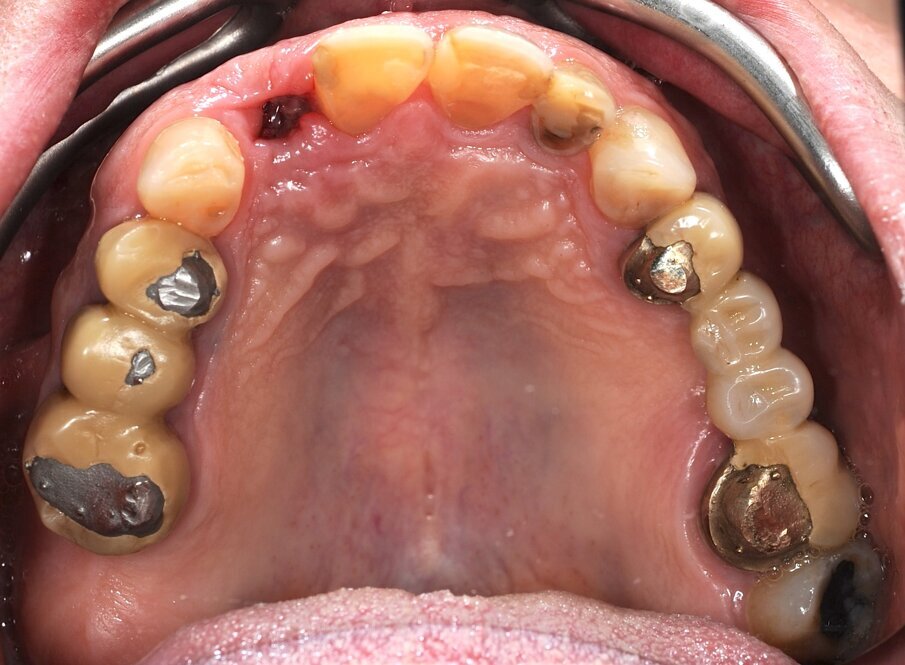

Un paziente di 66 anni, con anamnesi patologica di NIDDM ben compensato e cardio-vasculopatia ischemica in buon compenso farmacologico, si presenta alla nostra attenzione per ascesso parodontale alla radice residua del dente 1.2 e per multiple fratture dei manufatti protesici esistenti (Figg. 1-6). È evidente la presenza di grave malocclusione con perdita di VDO, usure e fratture dei restauri protesici e dei denti residui, presenza di abfractions cervicali. Il paziente evidenzia alla visita modesta dolenzia muscolare alla palpazione, specie a carico dei muscoli pterigoidei mediali e temporali, apertura della bocca ridotta e lieve rumorosità delle TMJ.

L’infezione a carico della radice del dente 1.2 è immediatamente attribuibile a frattura verticale con sondaggio positivo di 9 mm (Fig. 7). Estratta la radice di 1.2 fratturata, il paziente richiede una riabilitazione protesica fissa all’arcata superiore che preveda il minor numero possibile di interventi endodontici e chirurgici. Viene da noi proposta una riabilitazione protesica full arch che consenta, previo studio del caso gnatologico e terapia interlocutoria con provvisori in PMMA, la definizione di un’occlusione a funzione sequenziale in TRP per l’aumento controllato della VDO e la stabilizzazione dei rapporti articolari, ora visibilmente compromessi.